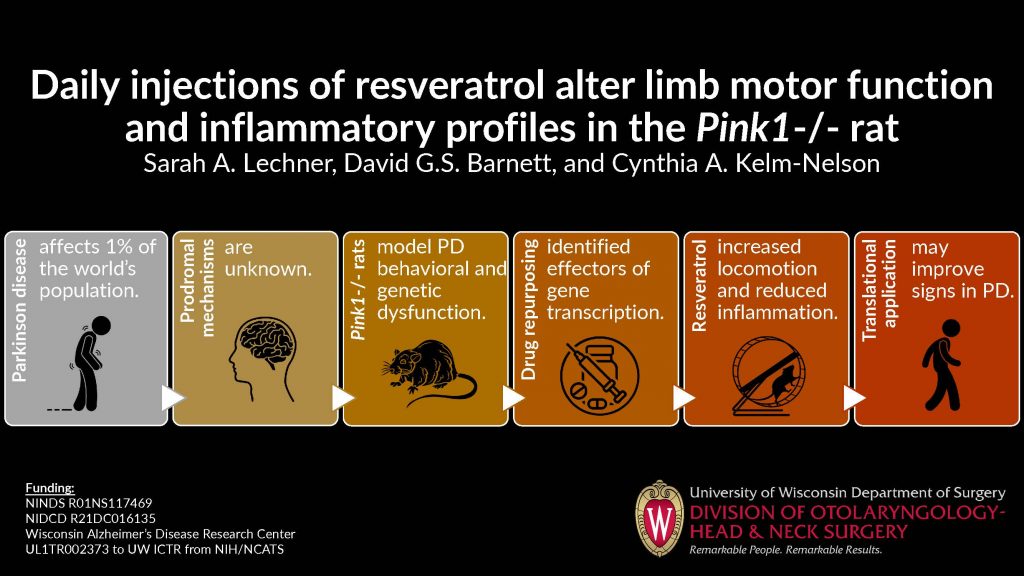

We also hold friendly competitions for the Best Surgery Science Image and the Best Visual Abstract, voted on by department members during the summit. Get a glimpse of the finalists and winners below. And for a complete overview, check out the 2023 Research Summit Program Book.

Best Visual Abstract

First Place:

Runner Up:

Runner Up: